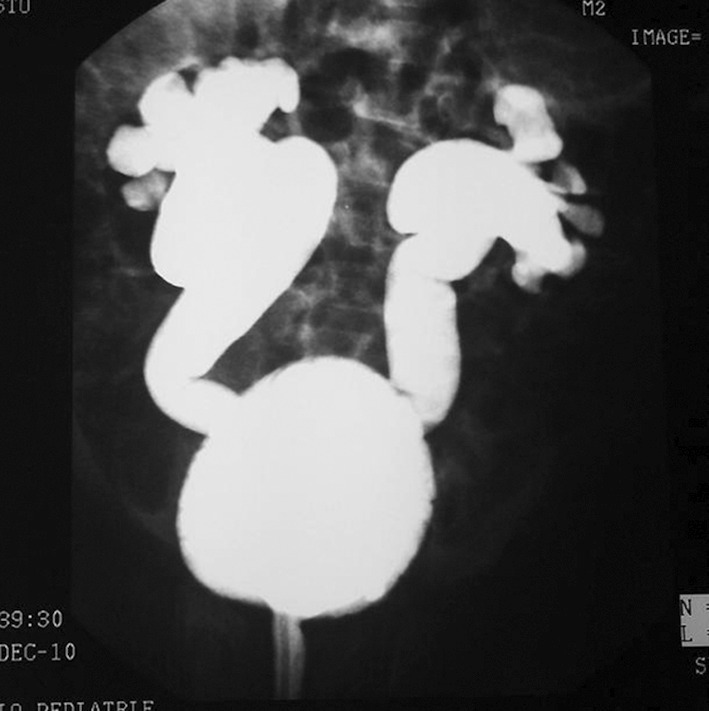

Le diagnostic radiologique est affirmé par la cystographie radiologique conventionnelle, examen de référence (figure).1-4 Les RVU sont dits de bas grade, intéressant une partie ou la totalité de l’uretère mais sans dilatation majeure des voies urinaires (grade 1, 2 et 3) et de haut grade (4 et 5), s’étendant à la totalité de l’uretère avec dilatation marquée et/ou reflux intrarénal.